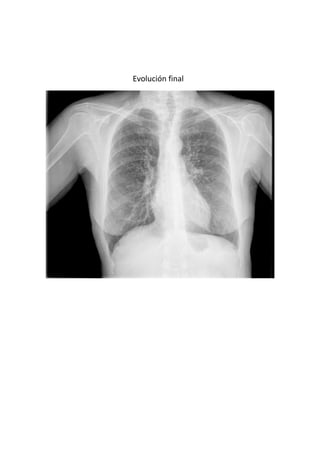

Este documento presenta 7 casos de patología torácica que serán discutidos en una sesión de interpretación radiológica. El objetivo es que los asistentes tomen notas aclaratorias durante la discusión interactiva de cada caso, en lugar de una mera explicación teórica. Los casos incluyen agenesia pulmonar derecha, situs inversus, estridor, neumonía con hemoptisis y enfermedad intersticial. El último caso involucra a un paciente de 86 años con tos y disnea que podría tener una consolidación en la base